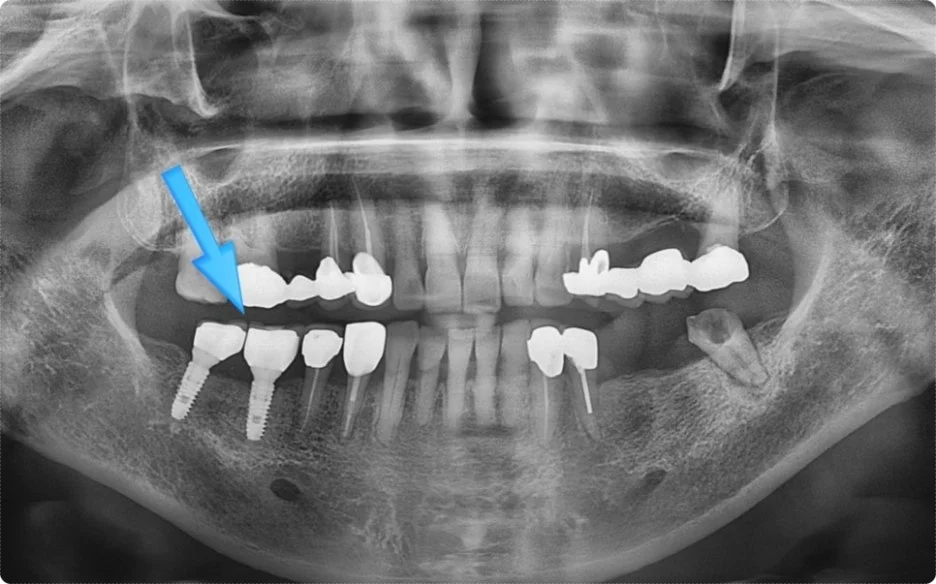

위 사진은 처음 내원하셨을 당시 촬영해 둔 영상입니다.

좌측 어금니 부위는 치아가 상실된 상태였고, 반대편인 우측에는 임플란트가 두 개 식립되어 있는 것이 확인되었습니다.

정확한 사유는 알 수 없지만, 환자분 말씀으로는 오른쪽 두 개의 임플란트를 같은 시기에 진행하면서도 각각 분리된 형태로 제작해 개별적으로 식립하셨다고 하셨습니다.

그 후 약 5개월이 지나, 임플란트가 흔들리는 증상을 느끼신 환자분이 본원으로 내원하셨습니다. 첫 방문 당시와 비교했을 때, 임플란트 사이 간격이 눈에 띄게 벌어진 상태였습니다.

단순히 나사만 느슨해진 경우라면 큰 문제가 없겠지만, 나사가 부러졌거나 임플란트 자체에 균열이나 파절이 생겼을 가능성이 높아 보였습니다.